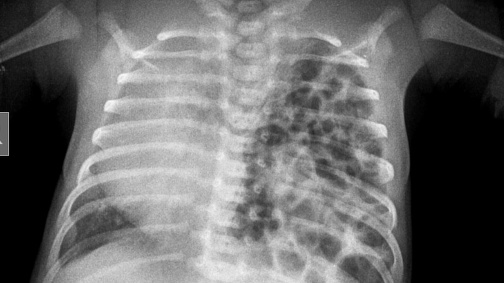

Chụp X-quang là một phương pháp chẩn đoán hình ảnh bằng cách sử dụng tia X-quang, là một loại bức xạ năng lượng cao. Tia X có thể xuyên qua các mô mềm và thành phần dịch trong cơ thể dễ dàng. Chụp X-quang có thể chẩn đoán được thoát vị hoành bẩm sinh sau khi sinh.

Hình ảnh X-quang có thể cho thấy hình ảnh dạ dày và ruột thoát vị vào lồng ngực, đẩy cấu trúc tim và phổi sang bên đối diện.